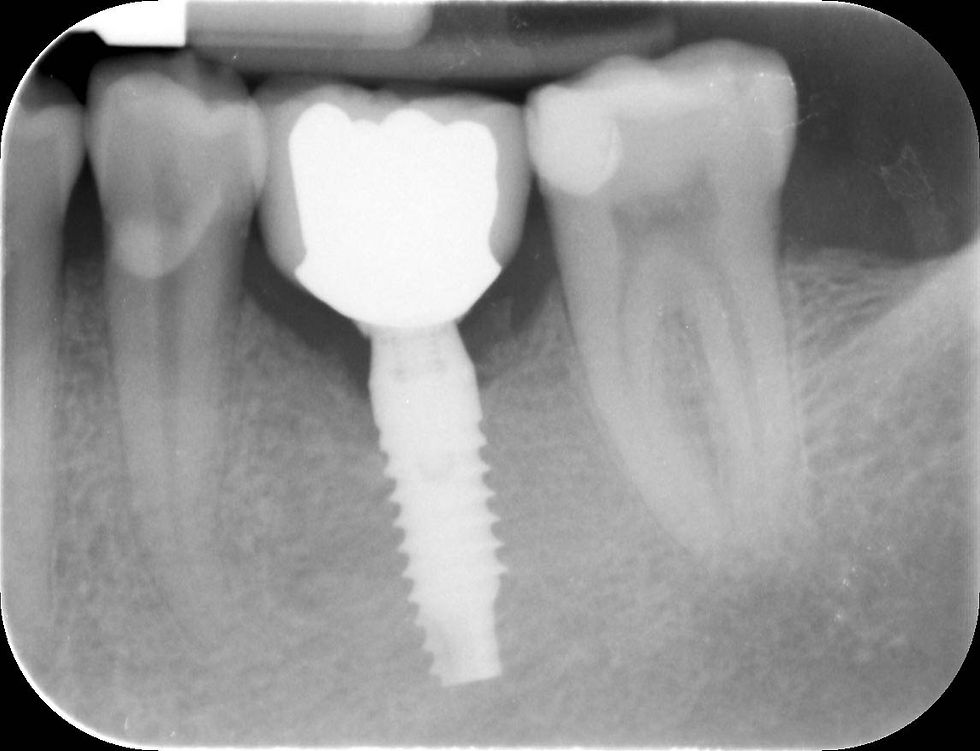

Radiograph at the time of the definitive crown delivery.